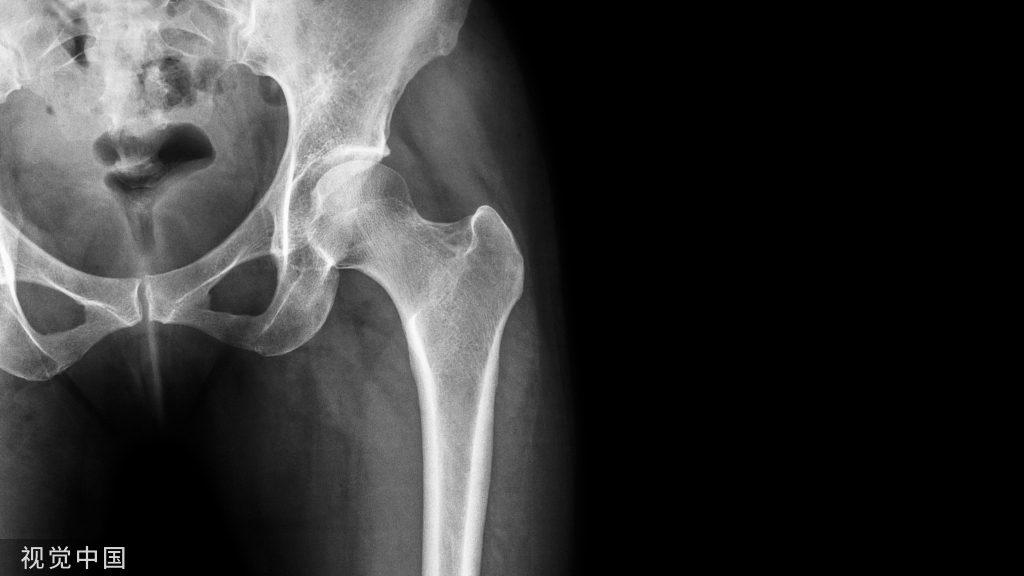

X线检查示骨纤维异常增殖症(Fibrous dysplasia ,FD)病变位于髓腔内,多见于骨干,病变区域多透亮,很少情况下出现高密度影(基质钙沉积时可出现),正常的骨小梁结构消失,代之以细颗粒“毛玻璃”样,有时病变周围的硬化骨带则可组成“果皮征”(rind sign)。

图示